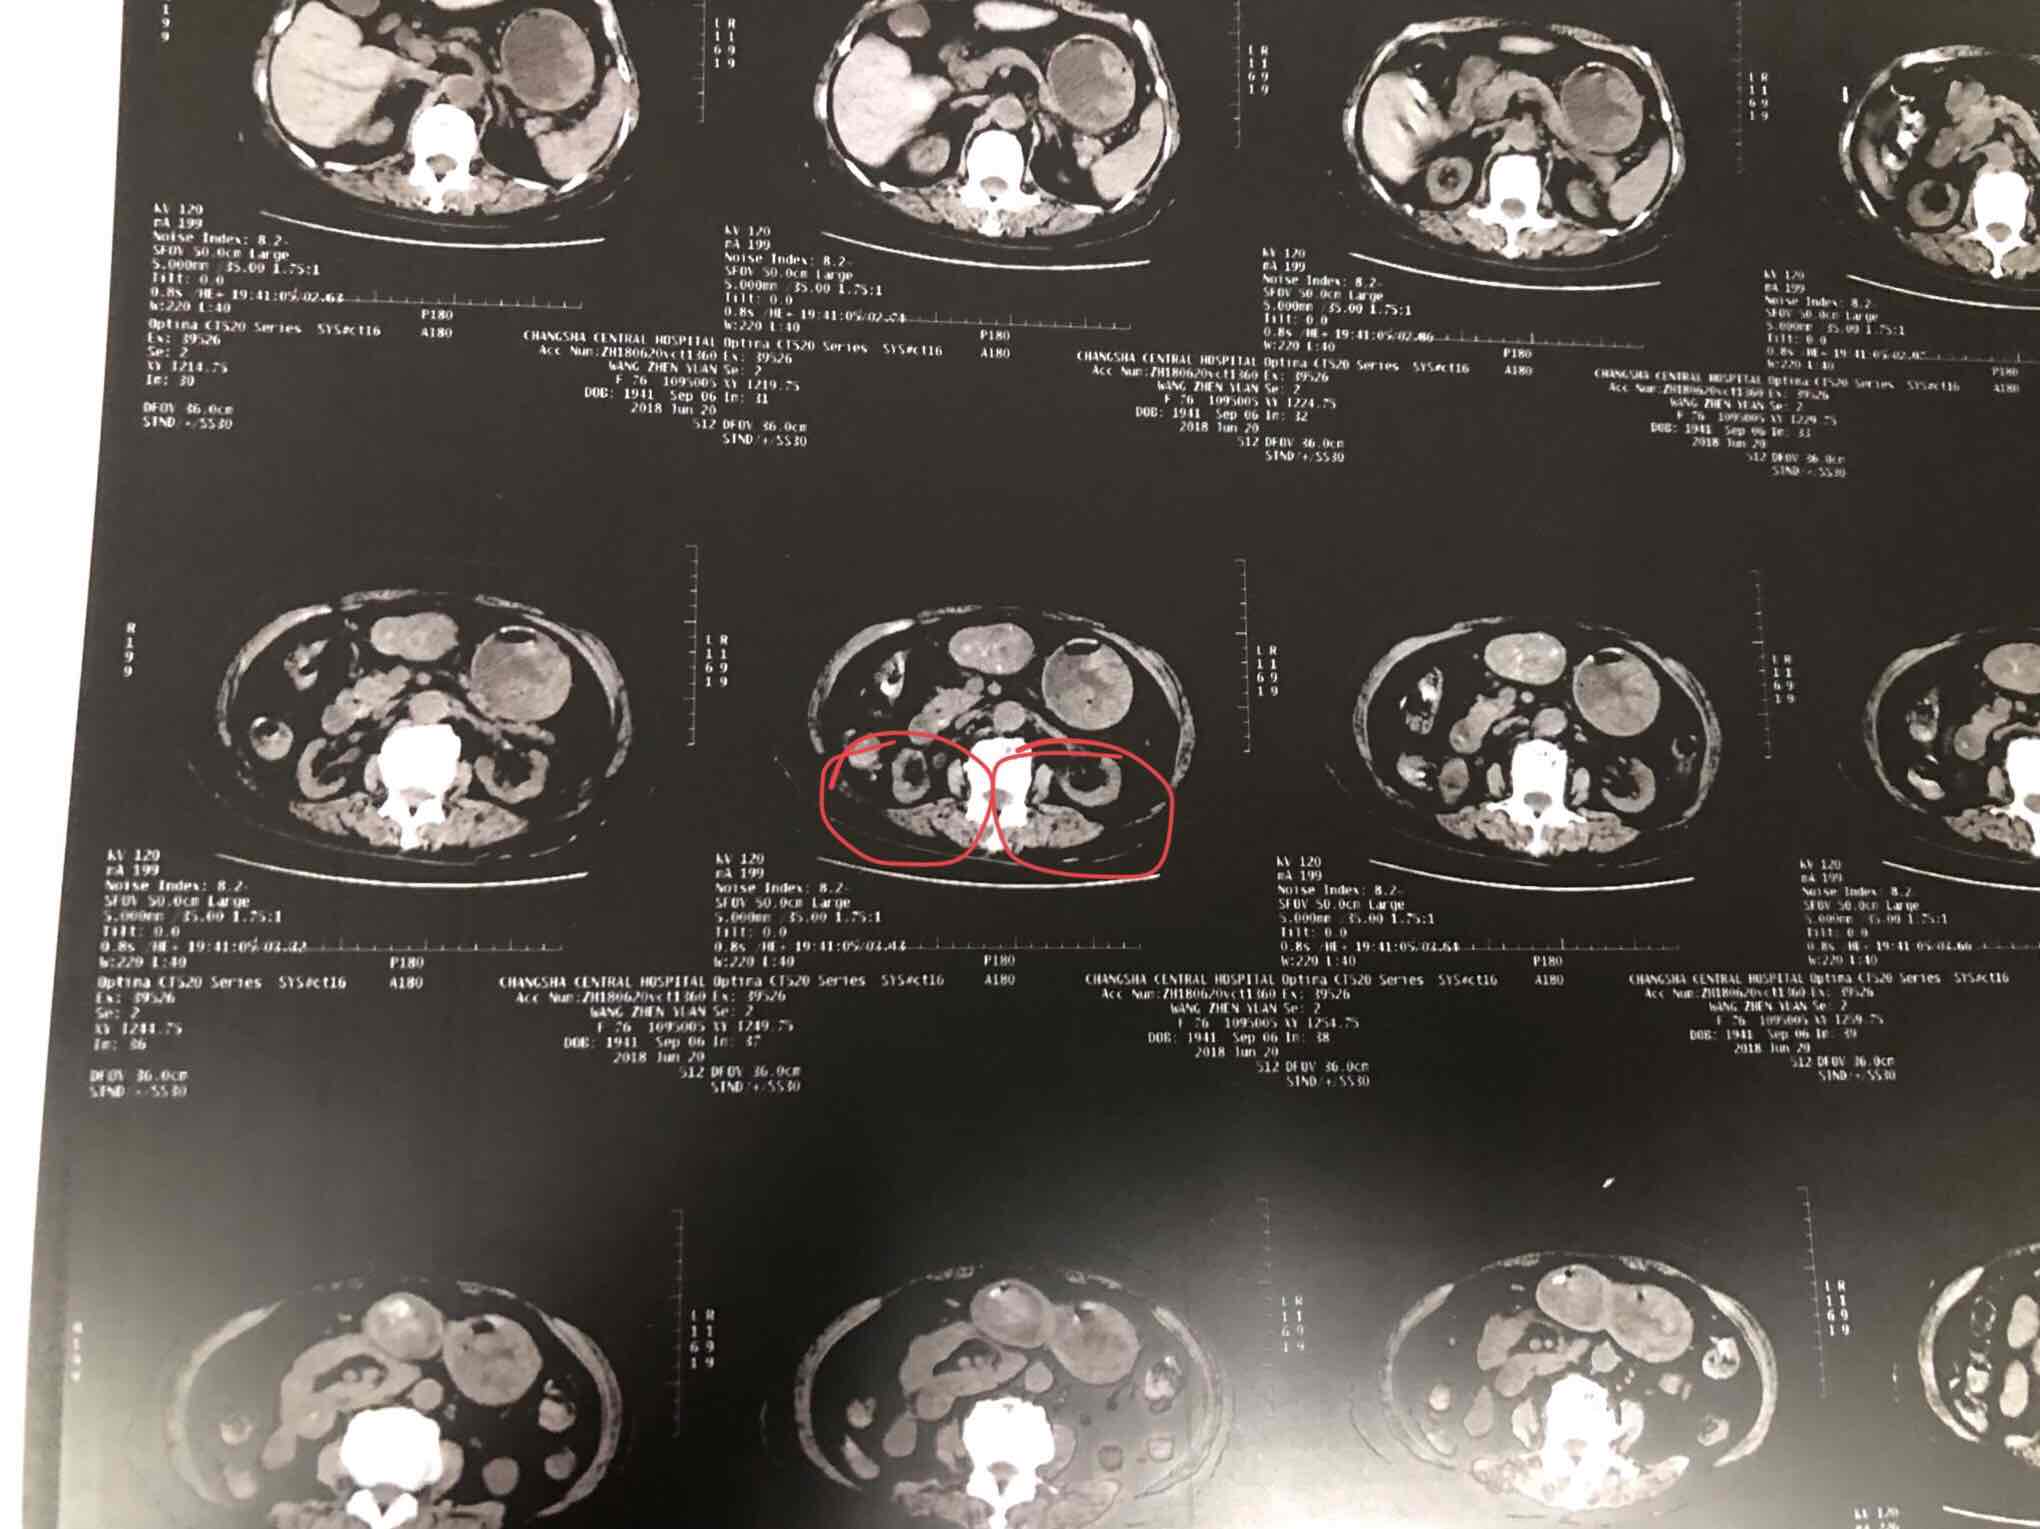

请问这个双肾ct考虑什么

图片尺寸3264x2448